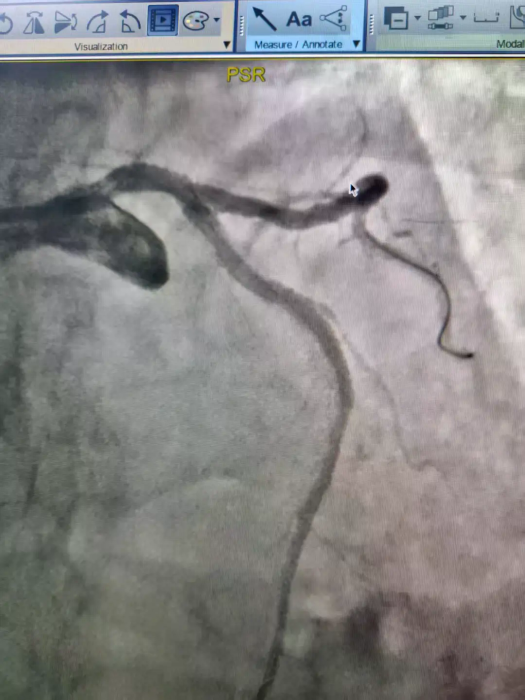

冠脉造影结果显示:患者左主干到前降支近中段重度钙化,伴70%~95%节段性狭窄,同时合并血栓,病变复杂、钙化严重,常规介入手术难度极大、风险极高。

△术前